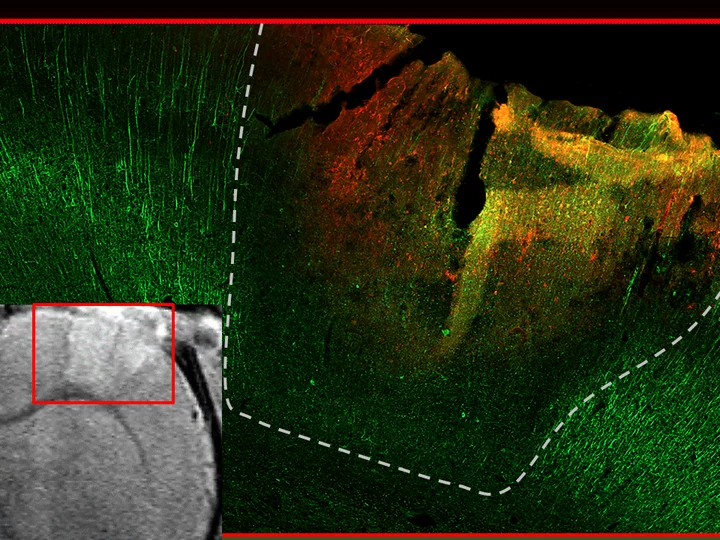

Neuronal landscape from healthy to injured rat brains: Top micrograph show healthy rat cortex with bright neuronal stain (Neurofilament light, NFL, green). Middle/bottom depict 1 month postinjury cortical contusion with neurodegeneration (NFL loss) and glial scarring (GFAP, red). Mediolateral traces of NFL loss for each injured rat contrast with normal averages (dotted green line with green variance band). Comparisons span both cortical gray matter (center) and corpus callosum white matter (right).

Internal validity is documented by aligning in vivo structural MRI hyperintensity (courtesy Neil Harris, UCLA) with postmortem acute loss of neuronal fiber signal  (Neurofilament light, green) around bleeds in the contused core visualized on immunofluorescence stained histological sections that are co-registered with one another in the same rat six hours after injury.